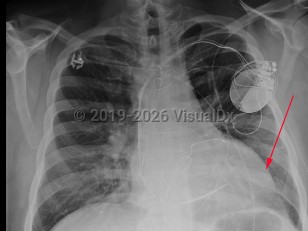

Chest pain, Pleural effusion, 50-59 year old Female

Pleural effusionPleural effusion

Hemothorax

Congestive heart failureCongestive heart failure